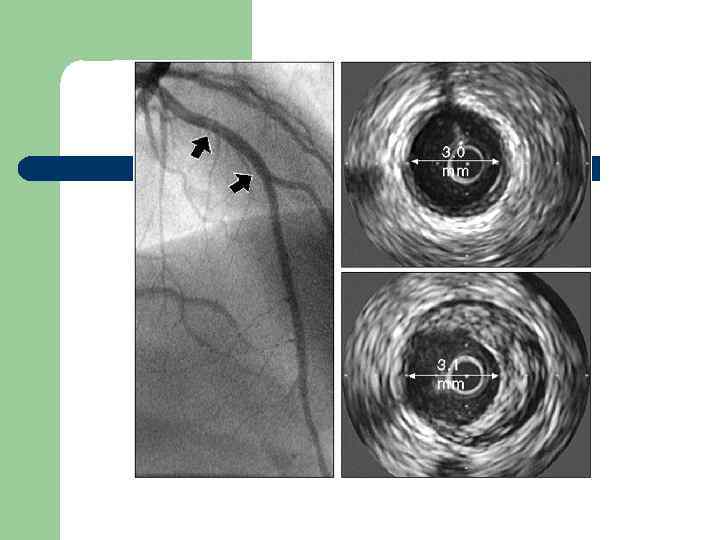

Концепция Glagov Рост атеросклеротической бляшки происходит в стенку сосуда без уменьшения просвета КА до тех пор, пока атерома не займёт 30 -40% толщины стенки. Именно эти бляшки лабильны, и они не визуализируются на КАГ.

Методы выявления атеросклеротических бляшек l l l Внутрисосудистое ультразвуковое сканирование коронарных артерий (визуализация бляшки, не выступающей в просвет) Чрезкожная коронарная ангиоскопия (визуализация просвета и поверхности бляшки) Чрезкожная коронарная термометрия (визуализация воспалённой бляшки) Компьютерная томография (кальцификация сосуда и бляшки) Магнито-резонансная томография (визуализация бляшки, оценка её стабильности)

PERSPECTIVE Оценка сегментов сосуда и выявление кальция методом ВСУЗИ Коронарная артерия в норме (эталон для дистального отдела) Bruining N et al. Coron Artery Dis. 2009; 20: 409 -414. Атеросклеротическая бляшка в коронарной артерии